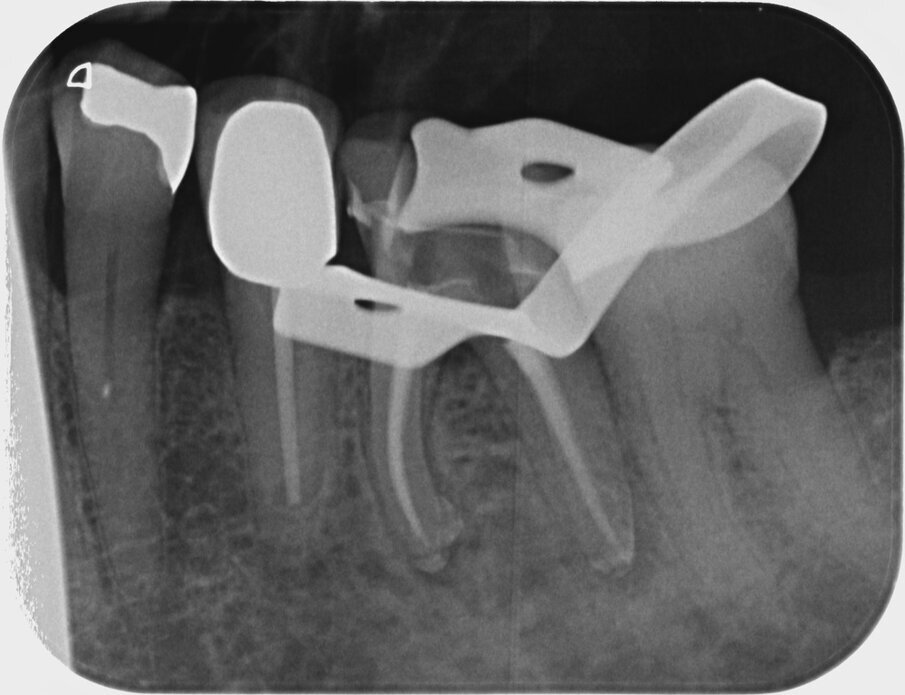

An 87-year-old female patient was referred to our clinic with pain in the third quadrant. The clinical and radiographic examination (using single-image radiography and CBCT) confirmed the suspicion of symptomatic periapical periodontitis at tooth #36 (Fig. 1). The preoperative single image suggested that a carrier-based root canal filling material had been used; furthermore, two ledges were visible in the mesial canal system. In addition, a second distal canal had to be assumed.

Fig. 3: Initial situation of mesial canals.

Fig. 4: Initial situation of distal canals.